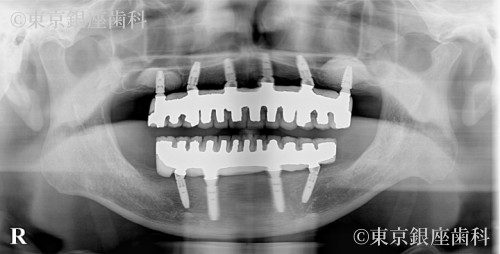

Before

After

施術内容 ワンデイインプラント

上下ワンデイインプラント(サイナスリフト併用)